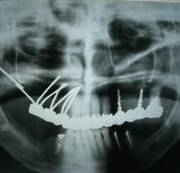

考古研究發(fā)現(xiàn),古埃及宮庭婦女就有采用骨內種植動物牙和象牙雕刻的人造牙的記載,出土的人類頜骨化石中還發(fā)現(xiàn)鑲有寶石或黃金雕成牙體形狀的植入物,它是牙種植體的原始雛形,最早可以追溯到公元前6000年。 中國有記載的種牙歷史比較遲 約800多年前 陸游:“近聞有醫(yī)以補墜齒為業(yè)者。” 800多年前,我國宋代樓鑰所著的《玫瑰集》中,也記載著了種牙。 宋代的大文豪陸游,不僅是一位豪放詩人,也是一位醫(yī)學愛好者。在陸游的《歲晚幽興》中說:“卜冢治棺輸我快,染須種牙笑人癡。”更可貴的是,他還在詩后面加了自注:“近聞有醫(yī)以補墜齒為業(yè)者。” 為了口腔健康,世界各國的人們想盡了辦法! 公元前4世紀,古希臘人就用人牙、動物牙、黃金和木材料來做人的假牙。 意大利西北部的伊特拉斯坎人在公元前700年就開始制作假牙,然后用金制箍條固定在鑲牙者口中。 在18世紀曾有從事“獵牙”者。1815年的滑鐵盧戰(zhàn)役留下的巨大牙齒資源,那一仗,拿破侖損失了3萬將士,英普等聯(lián)軍損失了2.3萬將士,這幾萬套“滑鐵盧牙齒”整整服務了歐美一代鑲假牙的人。 為了一顆好牙,人類的道德底線被擊穿了。 曙光與低谷 30年代至60年代的徘徊不前 1947年,M. formiggini以鉭絲錐形體植入口腔頜骨 1947年,M. formiggini以鉭絲錐形體植入口腔頜骨,成功地完成了義齒修復,他被譽為口腔種植學的奠基人,口腔種植技術似乎看到了曙光。 但由于在五六十年代種植義齒的臨床應用過分超前于基礎研究,造成種植高失敗率。1973年,國際衛(wèi)生研究所和美國牙醫(yī)學會的牙科材料委員會經(jīng)調查,對種植義齒持否定態(tài)度,牙種植由此一度跌入低谷。 終于找到開啟金色大門的鑰匙 1952-1982年,現(xiàn)代口腔種植學開啟 1952年,Br?nemark發(fā)現(xiàn)骨和純鈦能發(fā)生結合, 基礎研究的突破帶來了質的飛躍 20世紀60年代,Br?nemark教授首次提出口腔植入體使用高純度的鈦金屬替代以往的黃金等貴金屬成為新的植入材料。他在動物實驗中發(fā)現(xiàn),骨組織與植入的純鈦種植體結合得異常牢固,形成了一個完美的整體。 基于此項研究結果,Br?nemark教授創(chuàng)立了全新的骨結合理論:即人體活的骨組織與鈦種植體之間發(fā)生牢固、持久而直接的結合。該理論的確立在種植體領域掀起了革命性的變化。 在有記載的7000多年口腔種植歷史中,人類一直站在這扇厚重的金色大門前,束手無策。Br?nemark教授重于找到了開啟金色大門的鑰匙,人類正式步入現(xiàn)代口腔種植學的殿堂。 在這30年中 Br?nemark教授和他的團隊 克服了無數(shù)的困難與質疑 由于厚積了幾千年的失敗經(jīng)驗,物理學家和牙醫(yī)們思想已經(jīng)被牢牢固化。他們認為非生物材料不可能融入活的生物組織——最初的炎癥和最終的排異是不可避免的,這個過程也會給病人帶來極大的痛苦。 Br?nemark教授的發(fā)現(xiàn)有悖“傳統(tǒng)智慧”,因此,即使在1965年Br?nemark教授為G?sta Larsson先生成功的進行了鈦種植體種入,前方的路途依然漫長而坎坷。 現(xiàn)代口腔種植學的起源一方面來自骨結合理論的確立,另一方面還源于Br?nemark教授建立起的現(xiàn)代口腔種植標準化操作流程,他所著的《OSSEOINTEGRATED IMPLANTS》一書是現(xiàn)代口腔種植學的第一座里程碑。 在1982年多倫多召開的牙科種植大會上,Br?nemark教授向與會者展示了其團隊在齒科種植體領域15年的工作成績。從骨結合理論的發(fā)現(xiàn)與應用,到大量的、全新整理的科學實驗數(shù)據(jù)以及世界第一例成功種植牙臨床病例,終于獲得了與會者廣泛的關注和認可。 1982年多倫多召開的牙科種植大會 向Br?nemark教授和他的團隊致敬! 在金色大道上高歌前行 Nobel Biocare 時代來了 1978年,諾貝爾工業(yè)集團與Br?nemark教授開始合作,1981年Nobelpharma AB公司成立,1996年,公司更名為今天的Nobel Biocare公司。 一 Br?nemark System® Nobel Biocare經(jīng)久耐用的Br?nemark System®,G?sta Larsson先生使用了該系統(tǒng),運行40年依舊穩(wěn)固如新。 二 NobelReplace® Tapered Replace Select™ Tapered NobelReplace® Tapered(諾保易配錐形)及Replace Select™ Tapered(易配精選錐形)模仿自然牙根的形狀,該設計在所有負重方案,包括即刻行使功能中,都能取得極高初始穩(wěn)定性。 更新、更領先的系統(tǒng) NobelReplace® CC (Conical Connection) NobelReplace® CC (Conical Connection)結合獨創(chuàng)的錐形種植體主體和緊密密封的錐形連接體,為您和您的患者提供了一種適用于所有適應證的美齒解決方案。種植體主體可模擬自然牙根的形狀,旨在實現(xiàn)各種負重治療方案(包括 Immediate Function-即刻行使功能)的較高初期穩(wěn)定性。 NobelReplace® CC (Conical Connection)2011年全球上市(2015年中國上市)。 三 NobelActive® NobelActive®是具有劃時代意義的種植體。其體部及螺紋設計可以在植入時使進行骨擠壓,即使在骨質受損的情況下,也可以獲得很高的初始穩(wěn)定性。這使之成為即刻種植的理想之選。另外,頂部帶鉆刃的反向切割槽,可以調整種植體方向,以獲得最佳修復方向。 NobelActive®2008年全球上市(2012年中國上市)。 四 NobelSpeedy®系統(tǒng) NobelSpeedy®系統(tǒng)即使在軟質骨中使用也有很高的初始穩(wěn)定性,操作高效省時,同時具有卓越的多功能性和享受修復靈活性,特別是在快速骨形成的愈合時期保持很高的穩(wěn)定性,確保長期成功。 All-on-4®治療概念由帶有外六角的NobelSpeedy®種植體發(fā)展而來。 什么是 All-on-4® 概念? 開發(fā) All-on-4 臨床解決方案的目的在于最大限度地利用可利用骨量并支持即刻負重。 四顆種植體支撐全口無牙頜: 2顆前牙種植體,直的 2顆后牙種植體,傾斜的 全口樹脂牙橋進行即刻、臨時、固定修復與負重。 All-on-4®是NobelBiocare的注冊商標